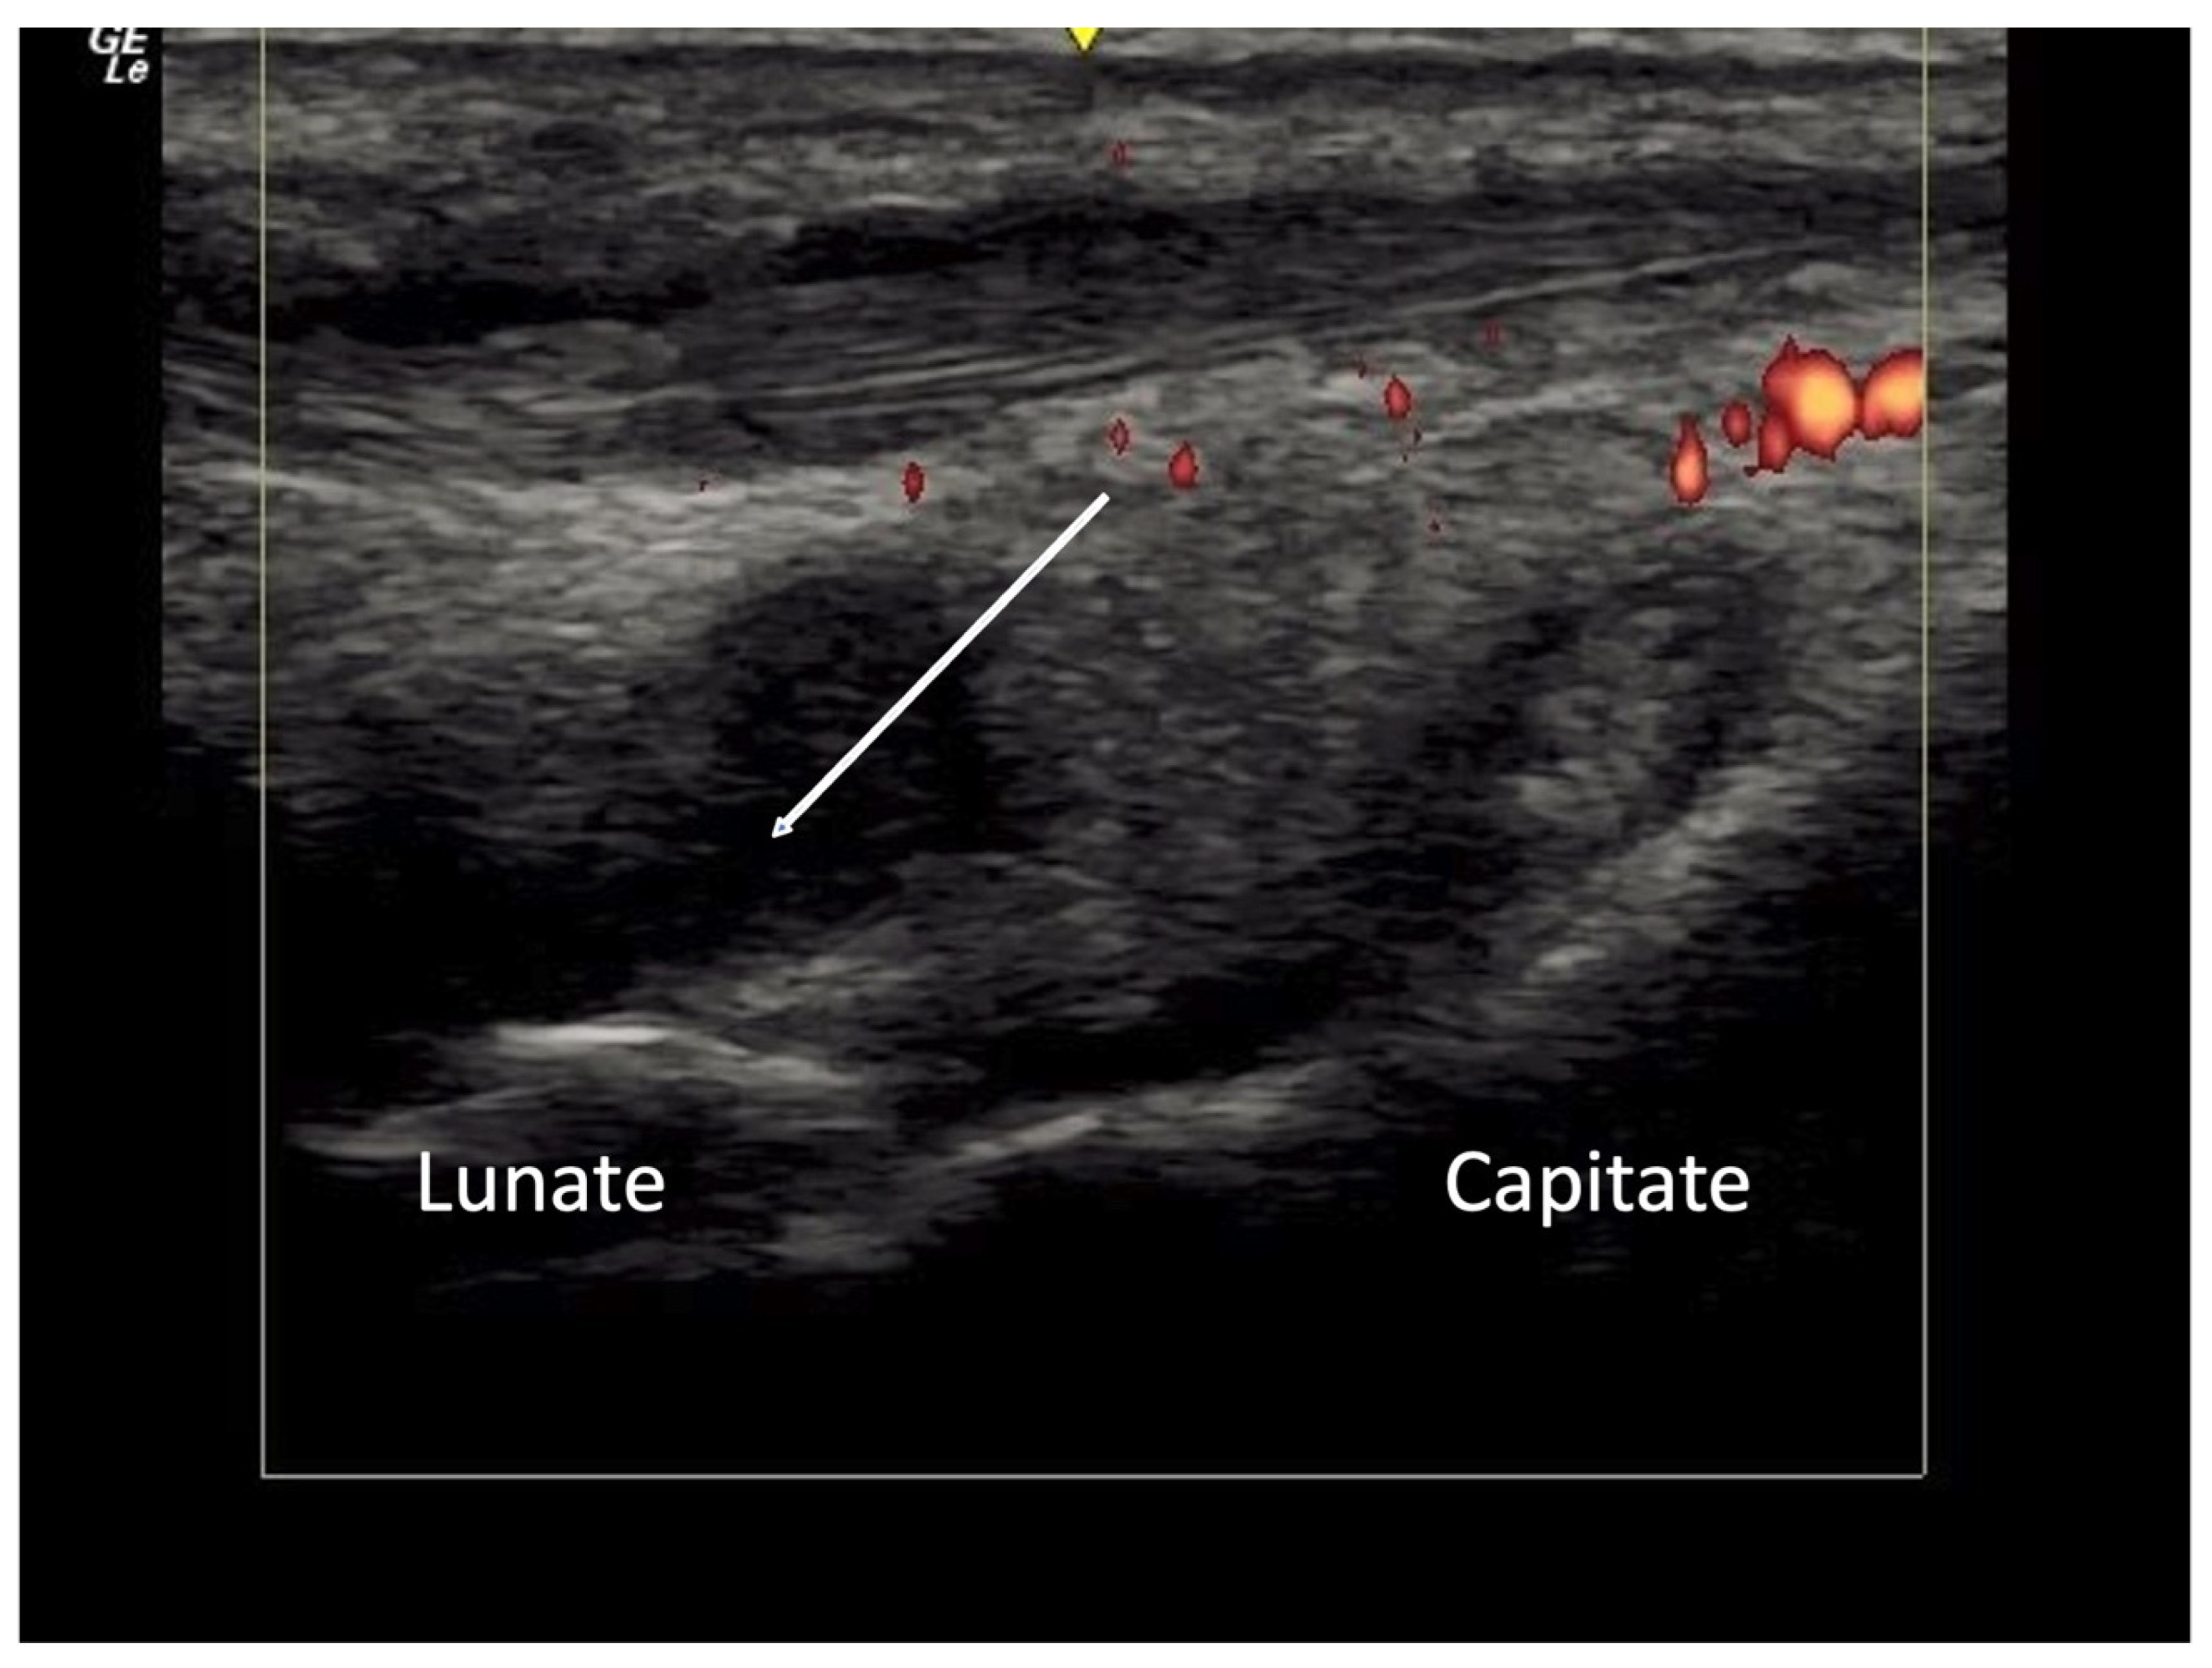

Carpal Tunnel Syndrome

4.2.2. Volar Aspect